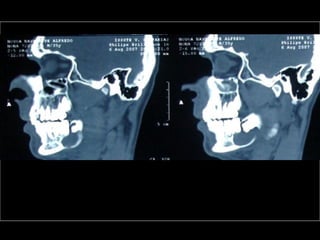

Tomografía computarizada

De seno maxilar corte sagital.

Area de implantación

Dentaria.

Material osteoconductor

para elevar el piso antral

Nuevo piso del seno y su

margen de seguridad para

contener el implante

Tomografía computarizada De senomaxilar corte sagital. Area de implantación Dentaria.

Nuevo piso delseno y su margen de seguridad para contener el implante dentario